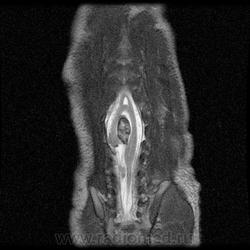

Диастематомиемия.

Наблюдение RadsWiki

Диастематомиемия (Тип 1)

Диастематомиемия (Тип 2)